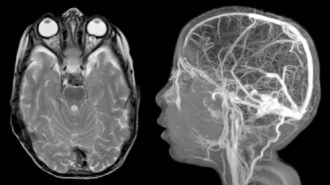

l’imagerie

elle élimine un processus tumoral et une hydrocéphalie ; elle montre la dilatation de la gaine arachnoïdienne du nerf optique, un aplatissement du globe, un soulèvement de la papille du nerf, une arachnoïdocèle intra-sellaire, une déformation du tronc cérébral.

elle étudie le drainage veineux qui peut être très anormal avec sténose ou atrophie des sinus avec circulation collatérale (ci-dessus), et hernie de villosités dans les sinus (ci contre).